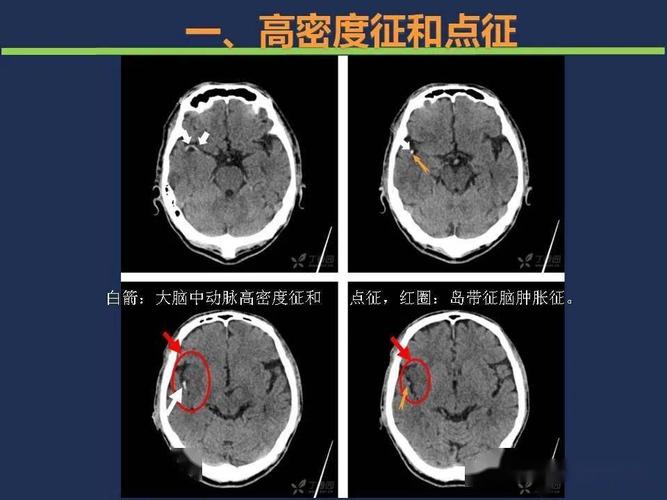

如何根据头颅ct预判超早期脑梗死?

头颅ct如何预判超早期脑梗死